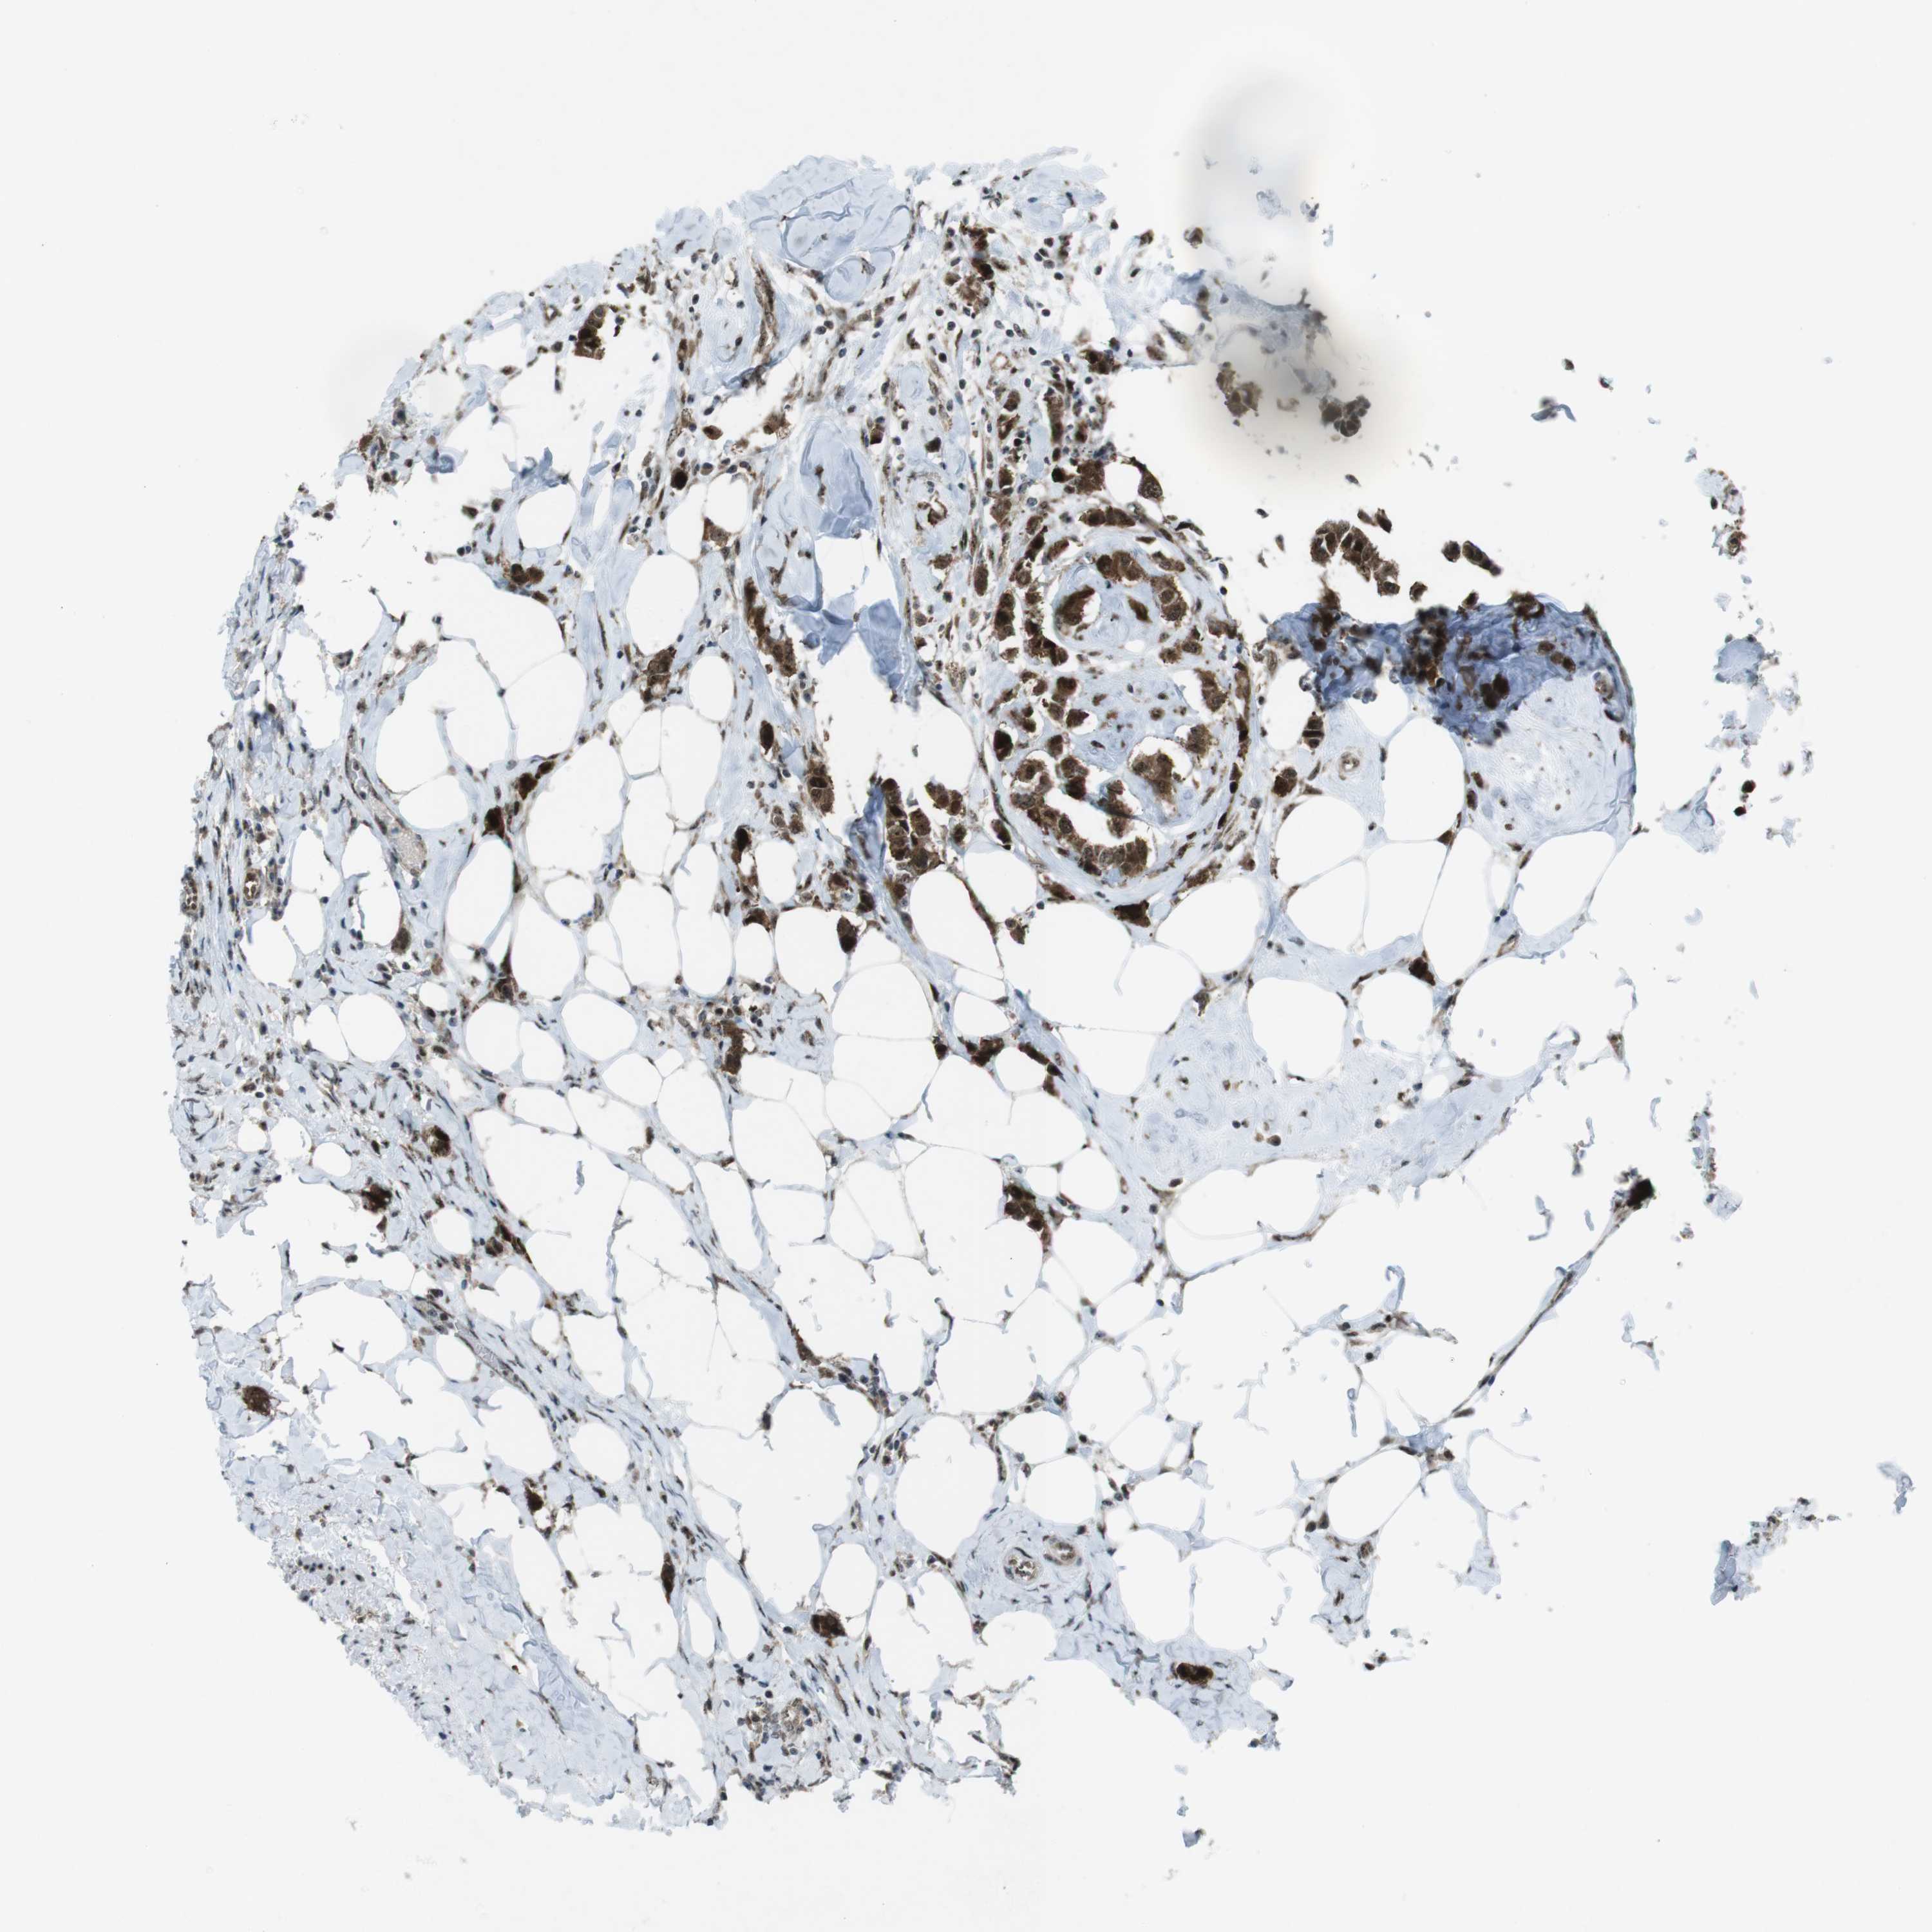

CANCER BREAST CANCER Show tissue menu

BRCA TCGA BRCA VALIDATION PROTEIN EXPRESSION